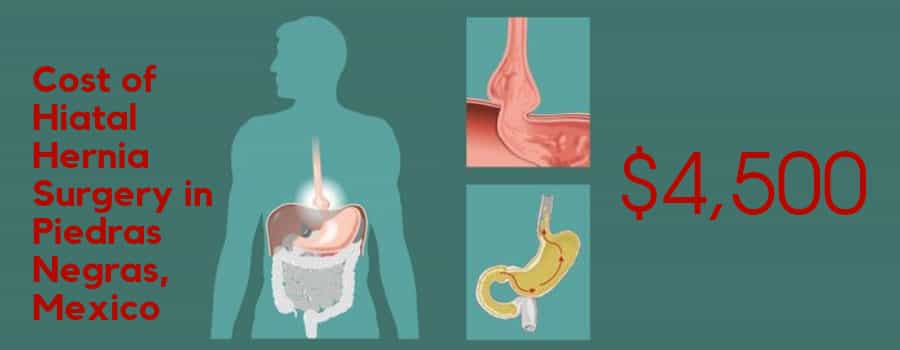

Cost: The average cost of Hiatal Hernia Surgery in Piedras Negras, Mexico $4,500

Note: Final prices are determined after physical evaluation and laboratory reports analysis.

Length to Stay: 5-7 days

Note: The duration may vary depending upon the condition of patient and the chosen procedure of treatment

Inclusions:

- All hospital fees with night stay

- Pre and post-operative consultations

- All medical fees (doctor fees, anesthesiologist and nursing staff)

- Post-surgery garment

Exclusions:

- Hotel or recovery house

- Preoperative lab work

- Airfare